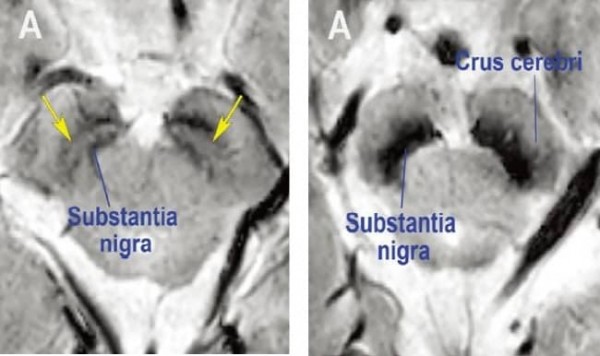

사진1. 정상 모양의 흑질(좌), 파킨슨병 환자의 흑질(우) MRI 영상

(흑질(substantia nigra)의 검정 부위 사이에 좌측 그림의 노란색 화살표가 가리키는 밝은 부분이 있으면 정상이고, 우측 그림처럼 검정색으로 메워지면 도파민신경세포가 소실된 환자이다.)